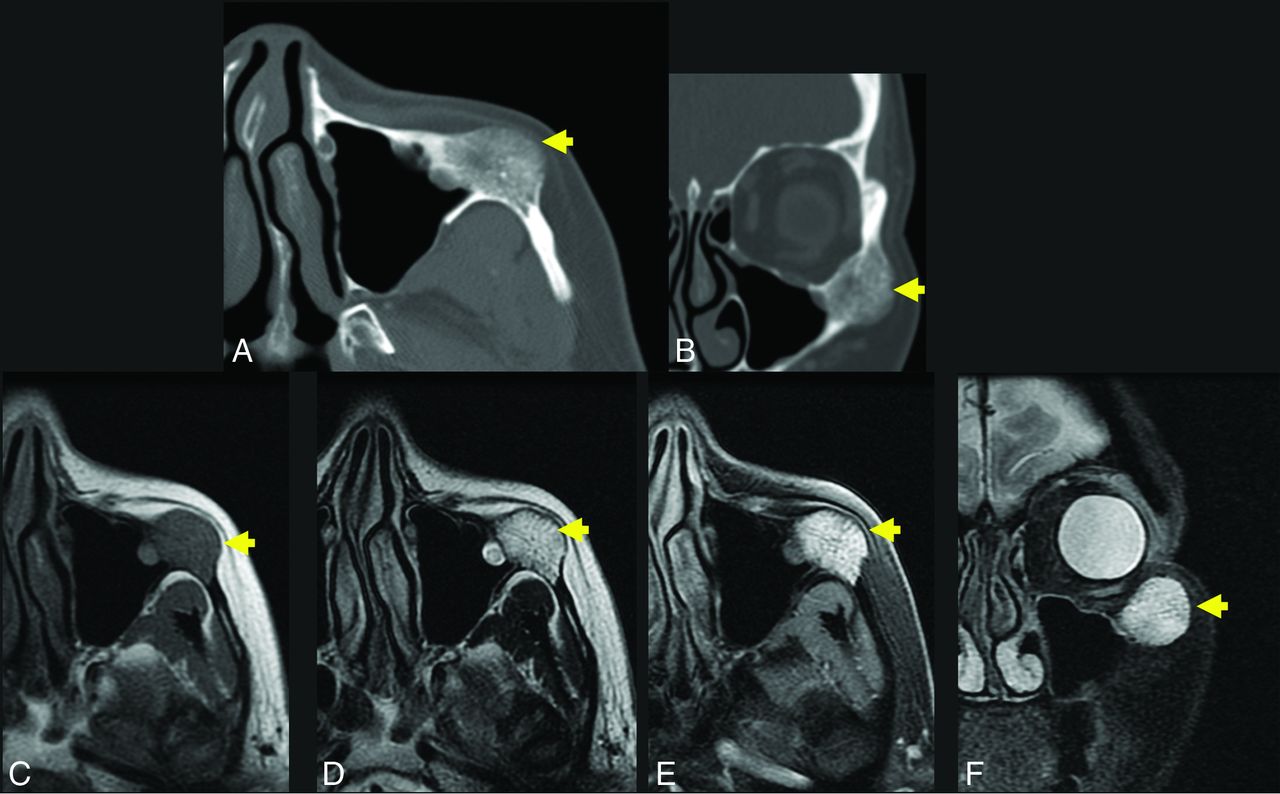

A 56-year-old woman with a palpable facial mass. The yellow arrow indicates a lesion in A–F. Axial (A) and coronal (B) thin-section CT in bone windows demonstrates an expansile, low-density lesion with internal coarsened trabeculae. The characteristic internal honeycomb pattern is typical of an IOVM. Axial T1 C– (C) and axial T1 C+ FS (D) sequences demonstrate a T1-intermediate, avidly enhancing lesion that extends beyond the cortical margin; the cortex is thinned but identifiable. Axial T2 FS (E) and coronal T2 FS (F) sequences demonstrate that the lesion is markedly T2 hyperintense. The diagnosis of IOVM was made on the basis of the characteristic imaging appearance, and the lesion remained stable on surveillance imaging for 3 years. C+ indicates with contrast; C–, without contrast.